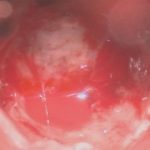

No.’25_74 摘出 前

No.’25_74  摘出 中

No.’25_74 摘出 後